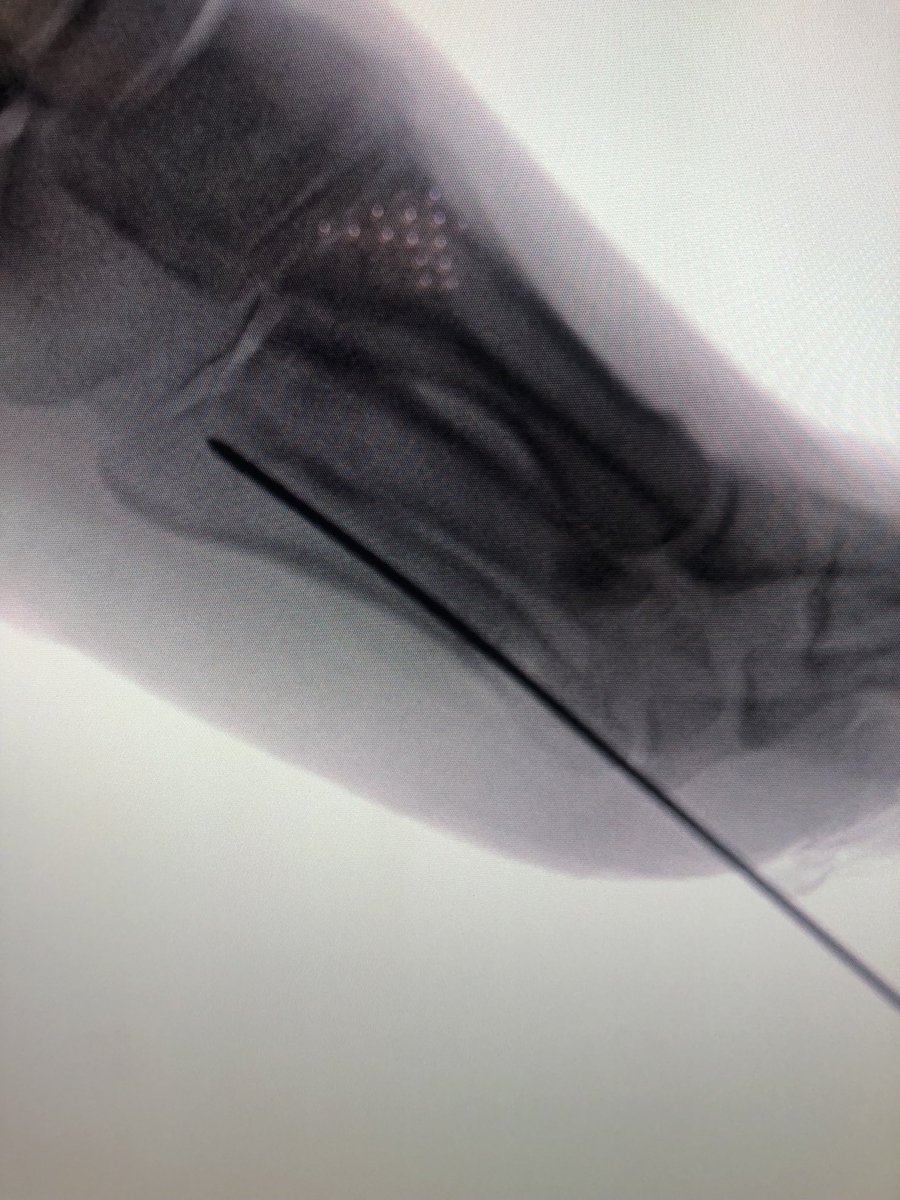

@traumaticum Synthes distal femur plate. Gave us more screw options with the distal flare than the proximal femur plate

@dzbro_ This I like. Still need to be a lucky bastard to sneak the screws around the nail though. What plate? Screws sit damn near perfectly

@dzbro_ ok, spell it out for me, i cant find a synthes distal femur plate similar to the one pictured?